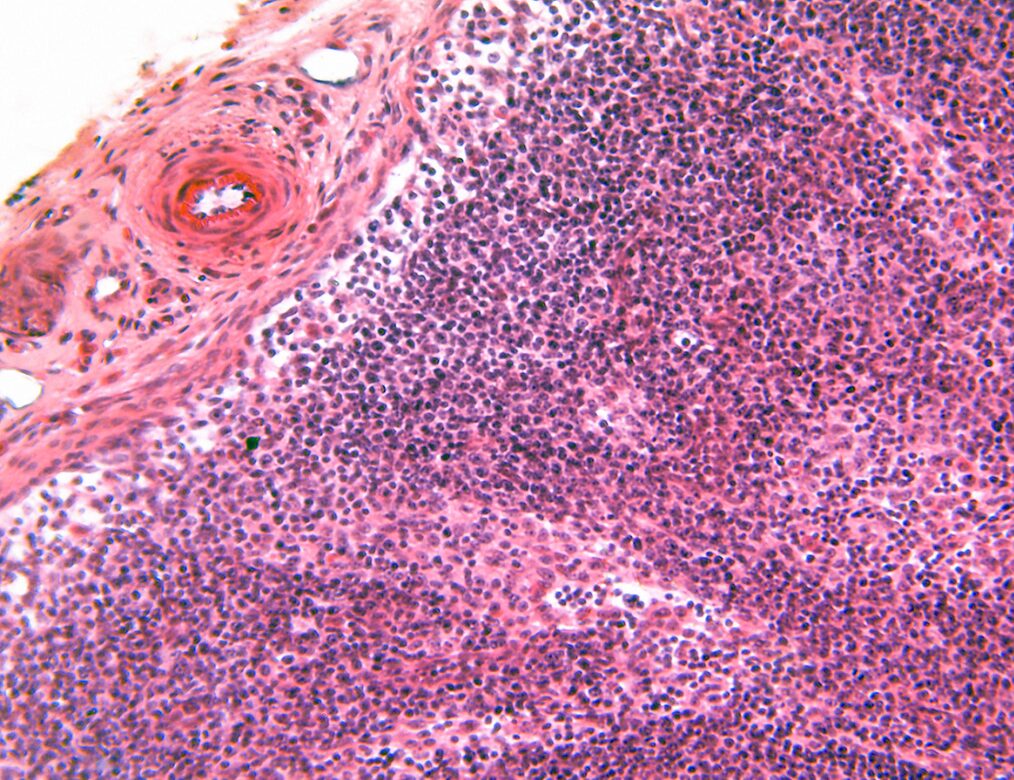

img